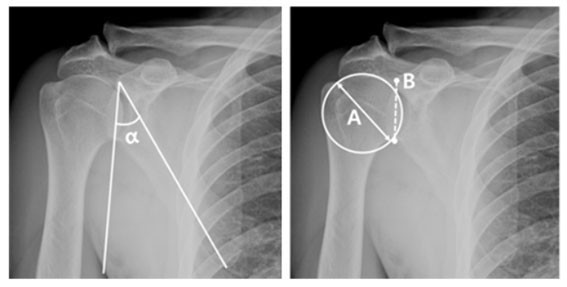

| | ¨Ï ¿Â¾ç½Å¹® | õ¾È¡¤¾Æ»êÃæ¹«º´¿ø Á¤Çü¿Ü°ú À¯À缺 ±³¼ö<»çÁø>°¡ ¿¬±¸ÇÑ °üÀý¿Í¼ø ¼Õ»ó¿¡ ´ëÇÑ ³í¹®ÀÌ ±¹Á¦ ÇмúÁö¿¡ °ÔÀçµÇ´Â ¼º°ú¸¦ °ÅµÎ¾ú´Ù.

Á¤Çü¿Ü°ú °ü·Ã ±¹Á¦ÇмúÁöÀÎ ¡®Journal of Orthopaedics¡¯¿¡ ¹ßÇ¥ÇÑ ¡®What are the anatomical predictive factors of degenerative superior labrum anterior to posterior lesion in rotator cuff tear?¡¯ ³í¹®Àº »óºÎ °üÀý¿Í¼ø ¼Õ»óÀÇ ÇØºÎÇÐ ¿øÀο¡ ´ëÇØ º¸°íÇÑ ³í¹®ÀÌ´Ù.

»óºÎ °üÀý¿Í¼ø ¼Õ»óÀ̶õ ¾î±ú»À °¡ÀåÀÚ¸®¸¦ µÏó·³ µÑ·¯½Î°í ÀÖ´Â ¼¶À¯ÁúÀÇ À§ÂÊ ¿¬°ñÀÎ »óºÎ °üÀý¿Í¼øÀÌ ÆÄ¿µÇ´Â °ÍÀ» ¸»Çϸç, ÀÏ»ó»ýȰ¿¡¼ ¾î±ú¸¦ ºÎµúÄ¡°Å³ª ÆÈÀ» ¤°í ³Ñ¾îÁú ¶§ ȤÀº ¿îµ¿ Áß ÆÈÀ» À§·Î Èֵθ£´Â µ¿ÀÛÀÌ °è¼ÓÀûÀ¸·Î ¹Ýº¹µÉ ¶§ ÁÖÀÇÇØ¾ß ÇÏ´Â ¾î±úÁúȯÀÌ´Ù.

ÈçÈ÷ Á߳⿡°Ô ¹ß»ýÇÏ´Â ¼Õ»óÀ¸·Î ±×µ¿¾È ´Ù¾çÇÑ ±âÀü¿¡ ´ëÇÑ ¿¬±¸°¡ ÀÖ¾úÀ½¿¡µµ ÇØºÎÇÐÀû À§ÇèÀÎÀÚ¿¡ ´ëÇÑ ¿¬±¸´Â Á¦ÇÑÀûÀ̾ú±â¿¡, À̹ø À¯À缺 ±³¼öÀÇ ³í¹®Àº ´Ù¾çÇÑ °ñ¼º ÁöÇ¥¿Í »óºÎ °üÀý¿Í¼ø ¼Õ»óÀÇ ¿¬°ü °ü°è¸¦ ºÐ¼®ÇÑ ¿¬±¸·Î¼ ±× ÀÇÀǰ¡ Å©´Ù.

| | ¡è¡è ¡ã»óºÎ °üÀý¿Í¼øÀÇ ÇØºÎÇÐÀû ¿øÀÎ ±Ô¸íÀ» À§ÇÑ °ñ¼º ÀÎÀÚ ÃøÁ¤ <»çÁøÁ¦°ø=¾Æ»êÃæ¹«º´¿ø> | ¨Ï ¿Â¾ç½Å¹® | | À¯À缺 ±³¼ö´Â ¡°À̹ø ¿¬±¸´Â ´Ù¾çÇÑ °ñ¼º ÁöÇ¥¿Í »óºÎ °üÀý¿Í¼ø ¼Õ»óÀÇ ¿¬°ü°ü°è¸¦ ºÐ¼®Çϰí, »óºÎ °üÀý¿Í¼øÀÇ ÇØºÎÇÐÀû ¿øÀÎ ±Ô¸íÀ» À§ÇÑ À¯ÀǹÌÇÑ ¿¬±¸¿´´Ù°í »ý°¢ÇÑ´Ù. ¾ÕÀ¸·Îµµ ȯÀڵ鿡°Ô ÃÖ¼±ÀÇ Áø·á¸¦ Á¦°øÇÏ°í ½ÇÁúÀûÀÎ µµ¿òÀ» µå¸± ¼ö ÀÖµµ·Ï ¿¬±¸¿¡µµ ¸ÅÁøÇϰڴÙ.¡±°í ¸»Çß´Ù.